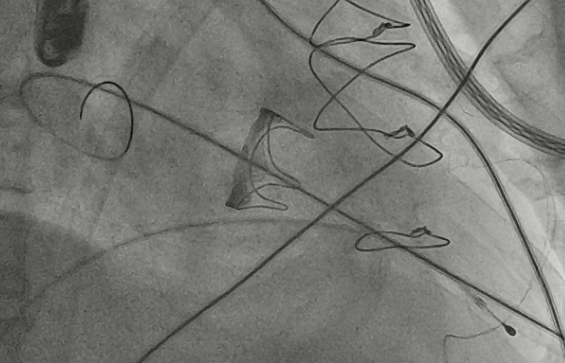

CDFI提示过瓣血流通畅

CDFI示少量瓣周漏

收缩期未见瓣周漏

左房内未见对比剂显影